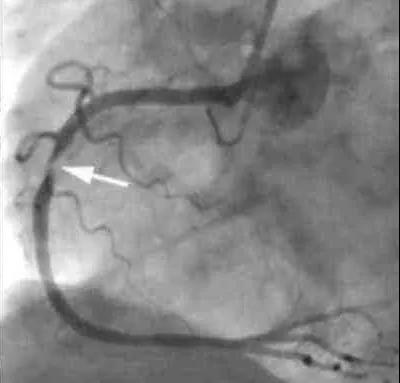

这位患者就到我们医院住院了。这个患者没有典型的劳累时胸闷或者胸痛症状,但有颈部紧缩感,再看看他的耳朵,确实有明显的皱褶,很有可能是冠心病。做冠脉造影,果不出所料,心脏三根血管均有狭窄,右冠脉重度狭窄,植入一枚支架。